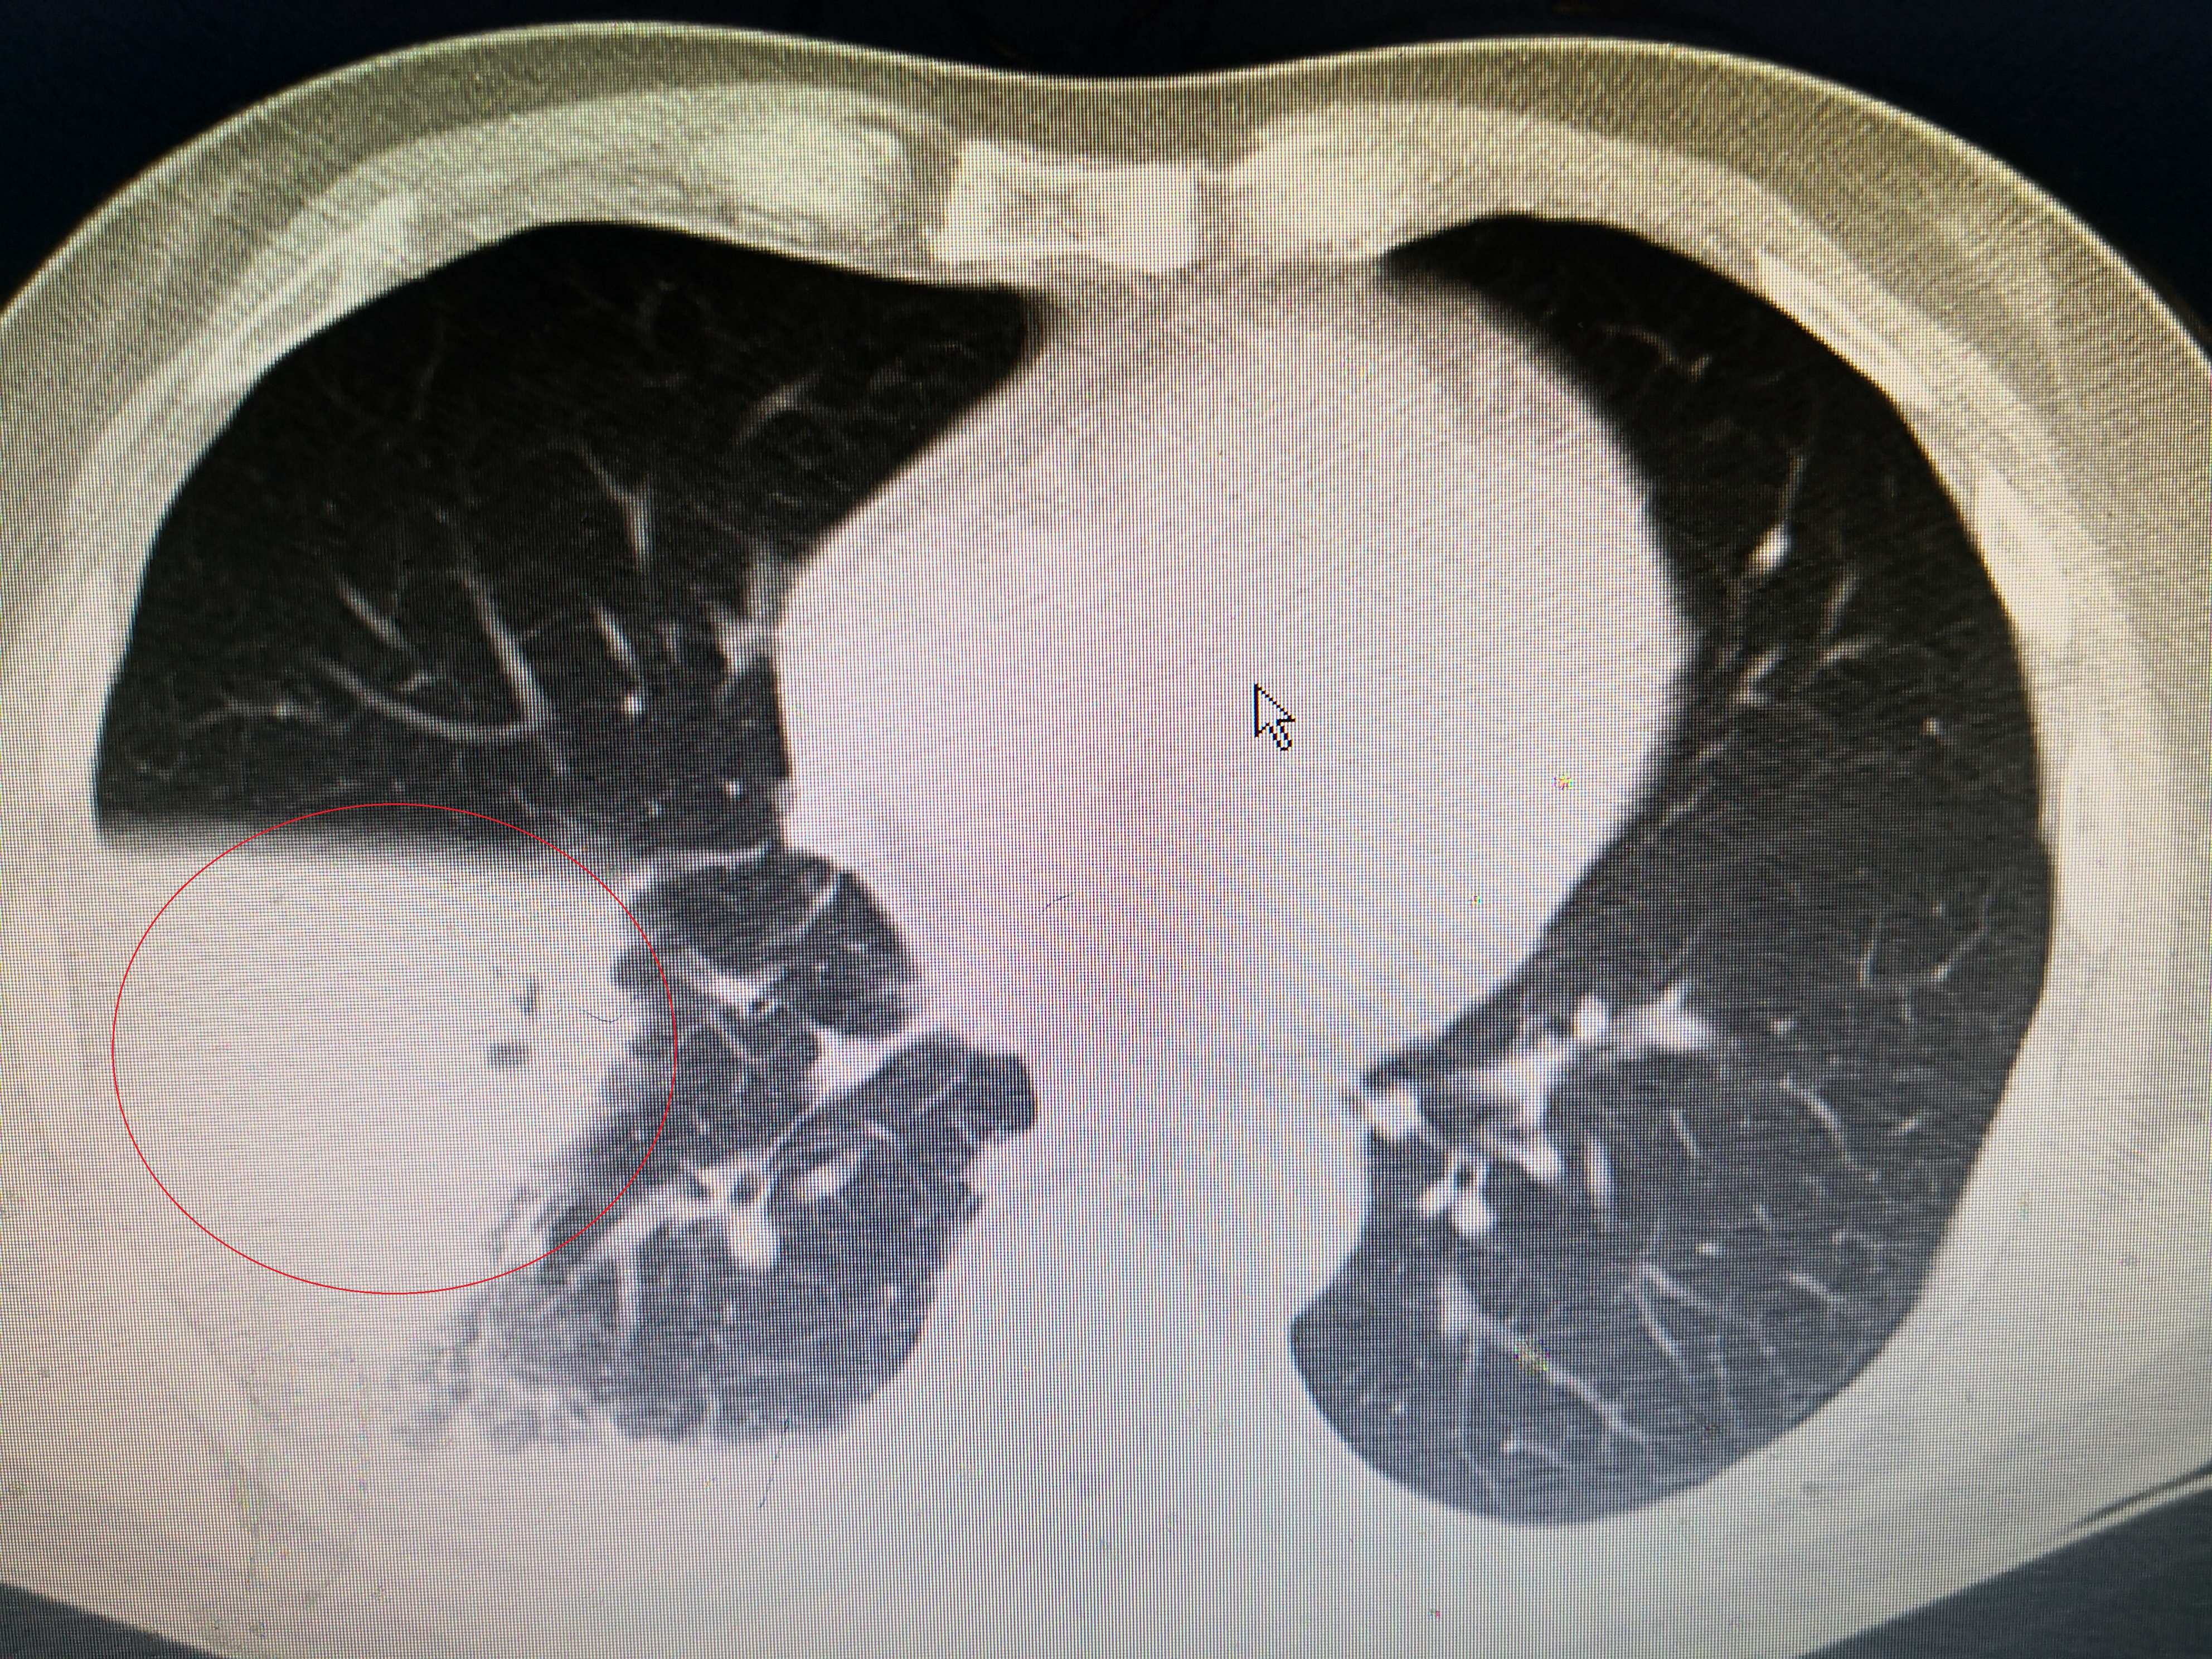

第一次氧分压降低

入院给予吸氧,喹诺酮+头孢二代标准抗感染方案,化痰治疗。通过5天治疗患者体温正常,不再咳嗽,精神状态好转,白细胞降到12.1×10^9,C反应蛋白降到46mg/l。氧分压90mmHg,恢复正常。该患者有顽固性呃逆,考虑和肺炎刺激膈肌有关,通过针灸、中药和口服巴氯芬治疗,也基本缓解。估计还有一周应该可以治愈出院。